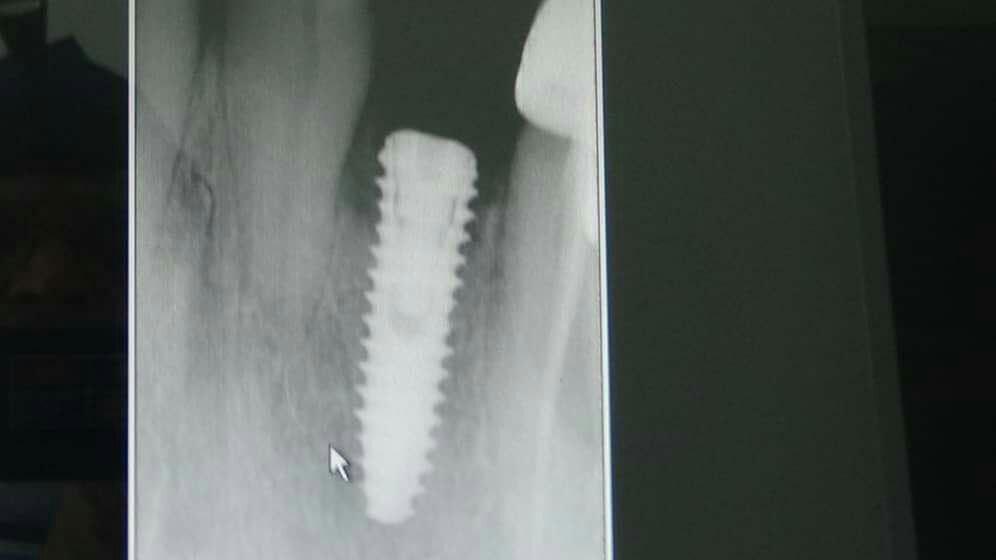

ایمپلنت چیست؟

ایمپلنت مجموع قطعاتی است که با جراحی داخل فک ثابت می‌شوند روی آن دندان مصنوعی قرار می‌گیرد و در نهایت ظاهری مشابه با دندان طبیعی پیدا می‌کند.

به‌طور کلی برای گذاشتن ایمپلنت دندان چندین مرحله باید انجام شود تا قطعات تشکیل دهنده در کنار یکدیگر قرار گیرند و بیمار بتواند به جای دندان طبیعی از آن استفاده کند. ایمپلنت از نظر ظاهری مشابه دندان طبیعی است و در دهان همان حس طبیعی را برای جویدن القا می‌کند و سوء هاضمه ایجاد شده بر اثر ناتوانی در جویدن غذا را برطرف می‌نماید.

ایمپلنت دندان برای جایگزین کردن یک یا چندین دندان از دست رفته کاربرد دارد و می‌تواند برای تمام دندان‌ها به صورت ثابت یا متحرک استفاده شود. در هر دو حالت فوق کلمه ایمپلنت استفاده می‌شود اما حالت دوم بیانگر معنی واقعی ایمپلنت است و به مجموعه‌ای از قطعات ایمپلنت گفته می‌شود و هر کدام از قطعات به تنهایی نام و کارایی مجزایی دارند.

در بعضی موارد مراجعه دیرهنگام فرد برای کاشت دندان (ایمپلنت) یا وجود کیست و تومورهای دهانی منجر به از بین رفتن فضای مناسب و کم شدن قطر و ارتفاع استخوان فک می‌شود که در این حالت، دندانپزشک قبل یا همزمان با جایگذاری فیکسچر، با استفاده از پودر و بلاک استخوانی و ممبرین (بایومتریال‌ها) استخوان را بازسازی کرده تا شرایط مناسب برای قرارگیری ایمپلنت مهیا گردد. در این مواقع طول درمان بیمار (آماده شدن استخوان برای جایگذاری ایمپلنت) بسته به شرایط بیمار از ۳ تا ۶ ماه طول می‌کشد و دندانپزشک به کمک عکس‌های رادیوگرافی می‌تواند روند درمان را دنبال کند و بهترین زمان را برای کاشت ایمپلنت تشخیص دهد.